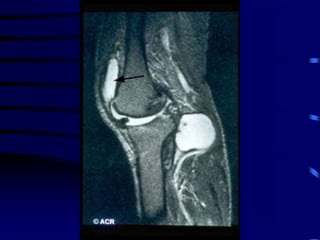

OSTEOARTRITIS

CORRELACION ANATOMO-RADIOLOGICA

PATOLOGIA RADIOLOGIA

Fibrilación y erosión cartilaginosa Pinzamiento articular

Prolifer. celular en hueso subcondral Esclerosis ósea

Intrusión de LS o contusión ósea Quistes subcondrales

Proliferación marginal Osteófitos

Distorsión capsular y ligamentaria Deformidad y desalineación

Factores Asociados a Progresión de

OA de Rodillas

• Edad avanzada

• Sexo Femenino

• Obesidad

• Nódulos de Heberden

• Baja ingesta de Vitamina C ?

• Baja ingesta de Vitamina D ?